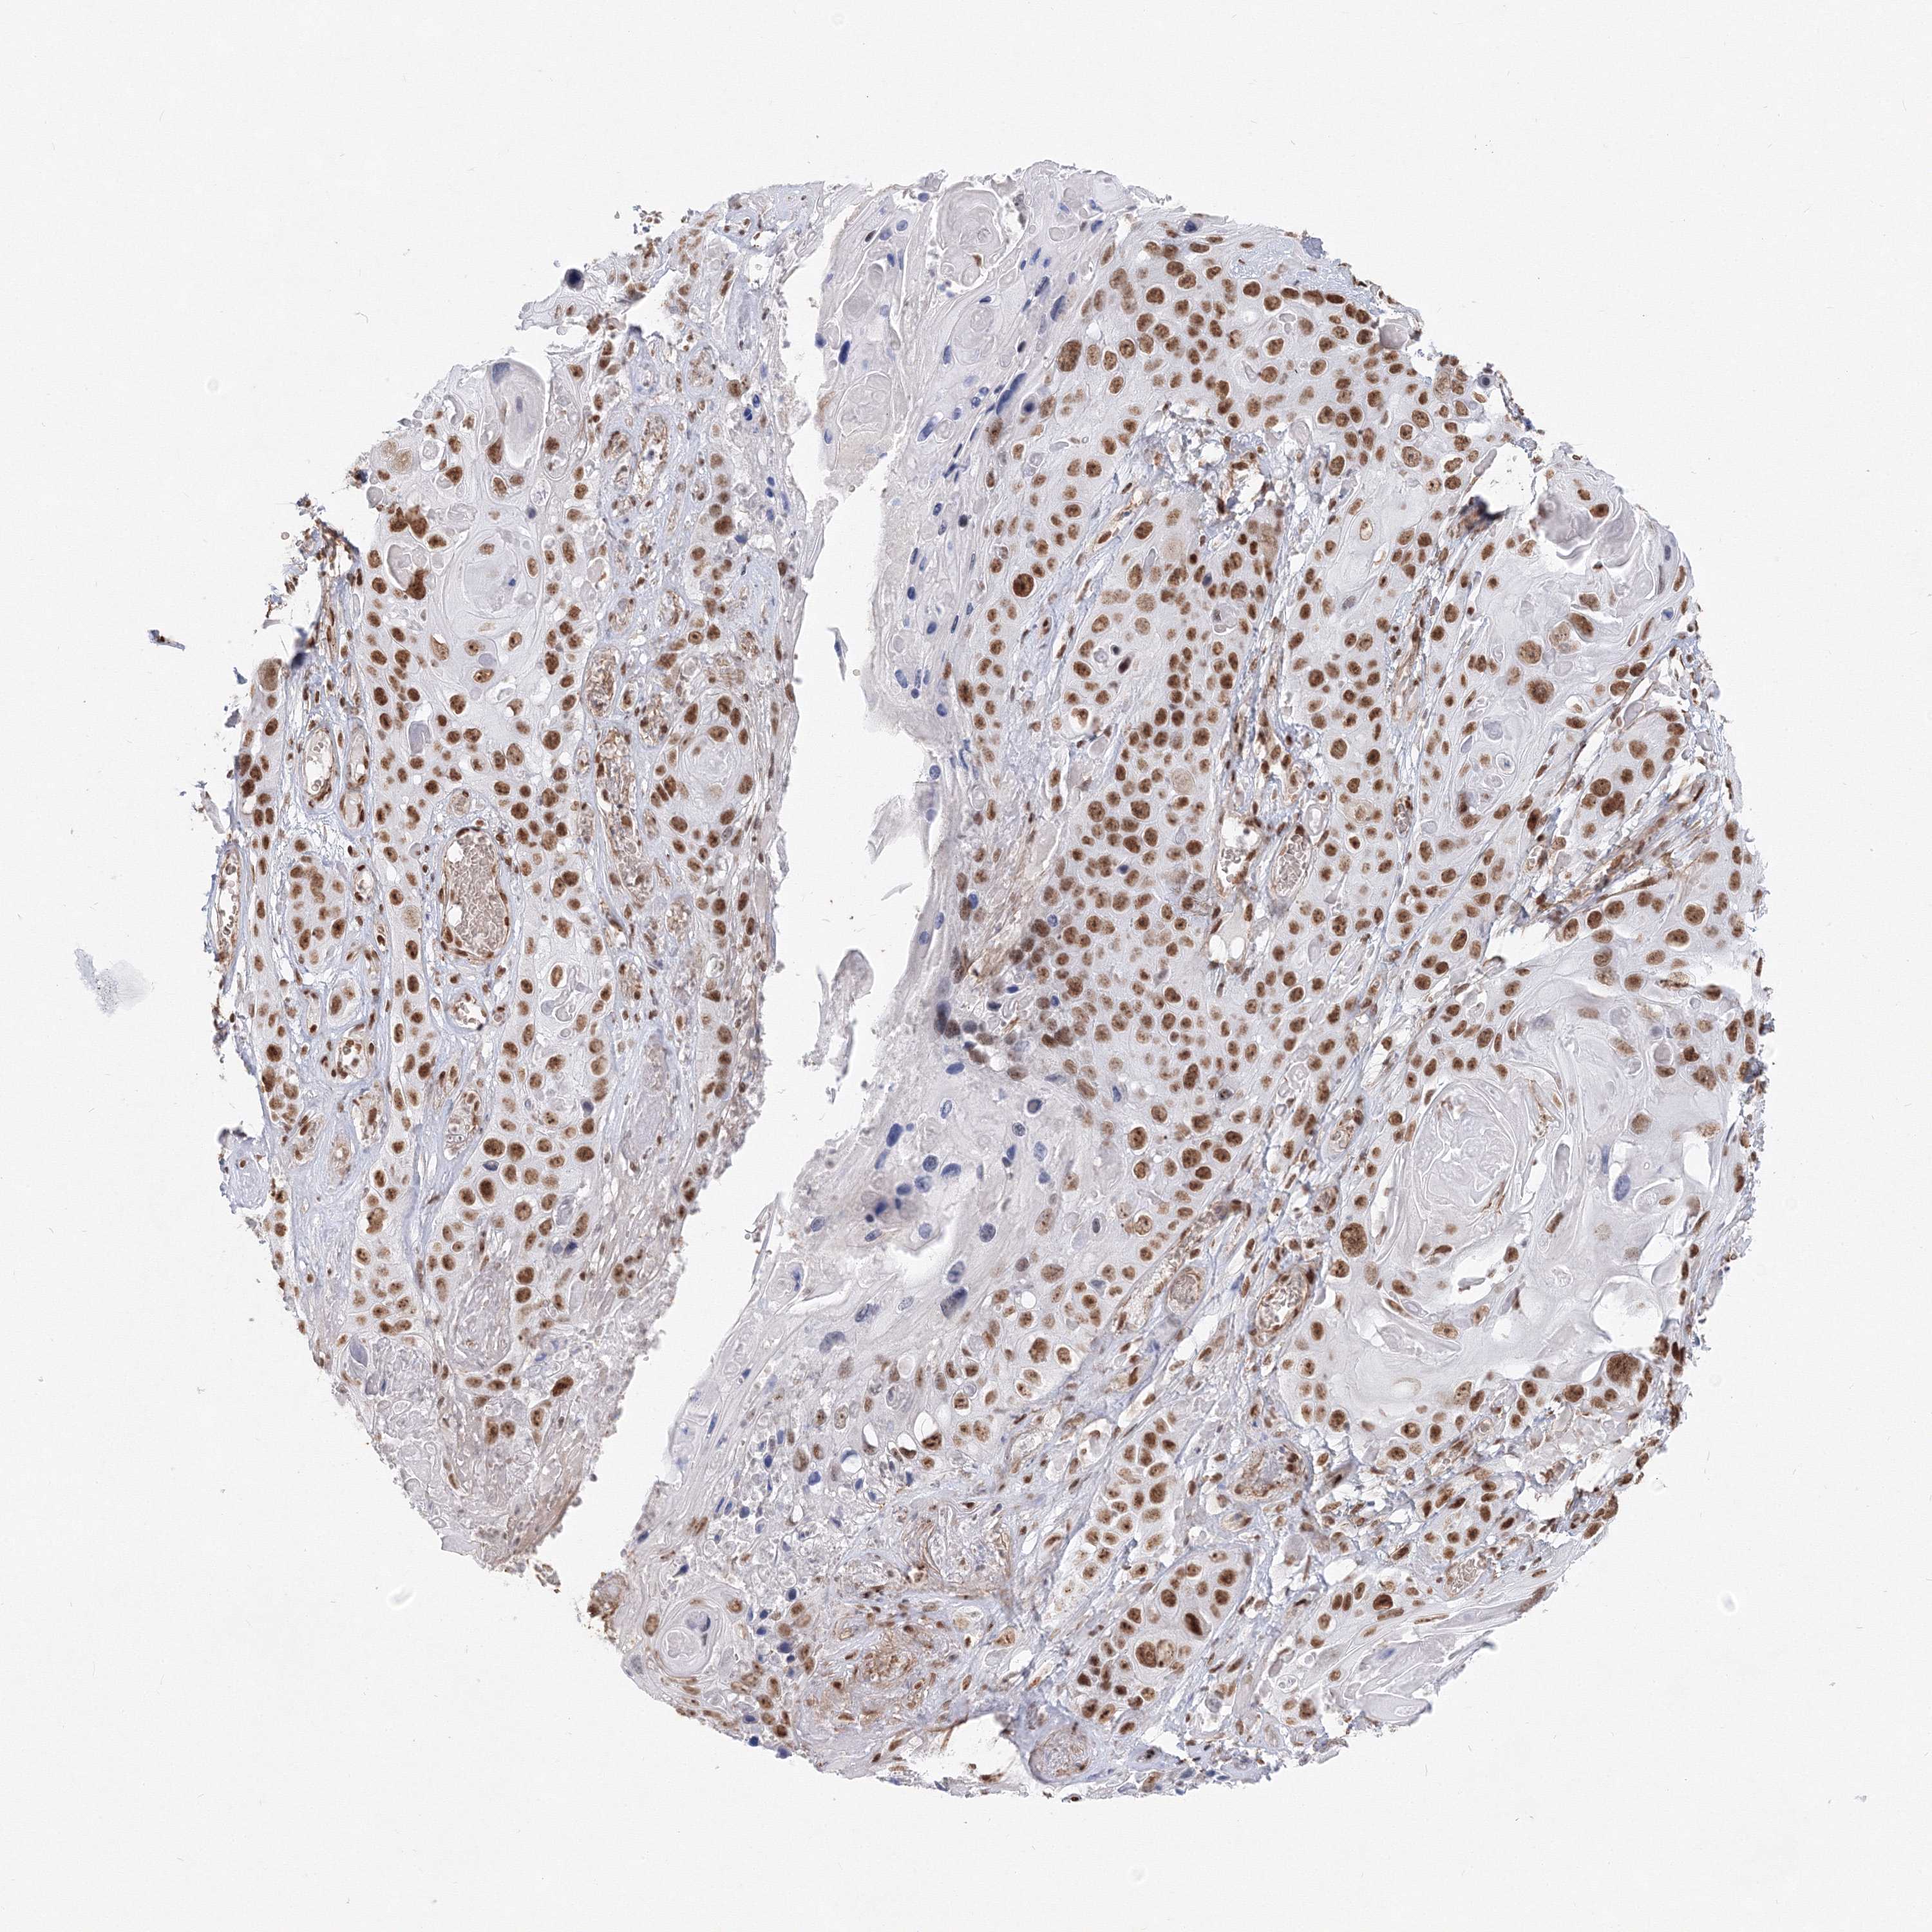

SKIN CANCER - Protein expressioni

A mouse-over function shows sample information and annotation data. Click on an image to view it in a full screen mode. Samples can be filtered based on level of antibody staining by selecting one or several of the following categories: high, medium, low and not detected. The assay and annotation is described here.

Each image is clickable and will lead to virtual microscopy that enables deeper exploration of all samples and also displays staining intensity scores, fraction scores and subcellular localization as well as patient and tissue information for each sample.

Antibody HPA036784

Staining

High

Intensity

Strong

Quantity

>75%

Location

Nuclear

Basal cell carcinoma